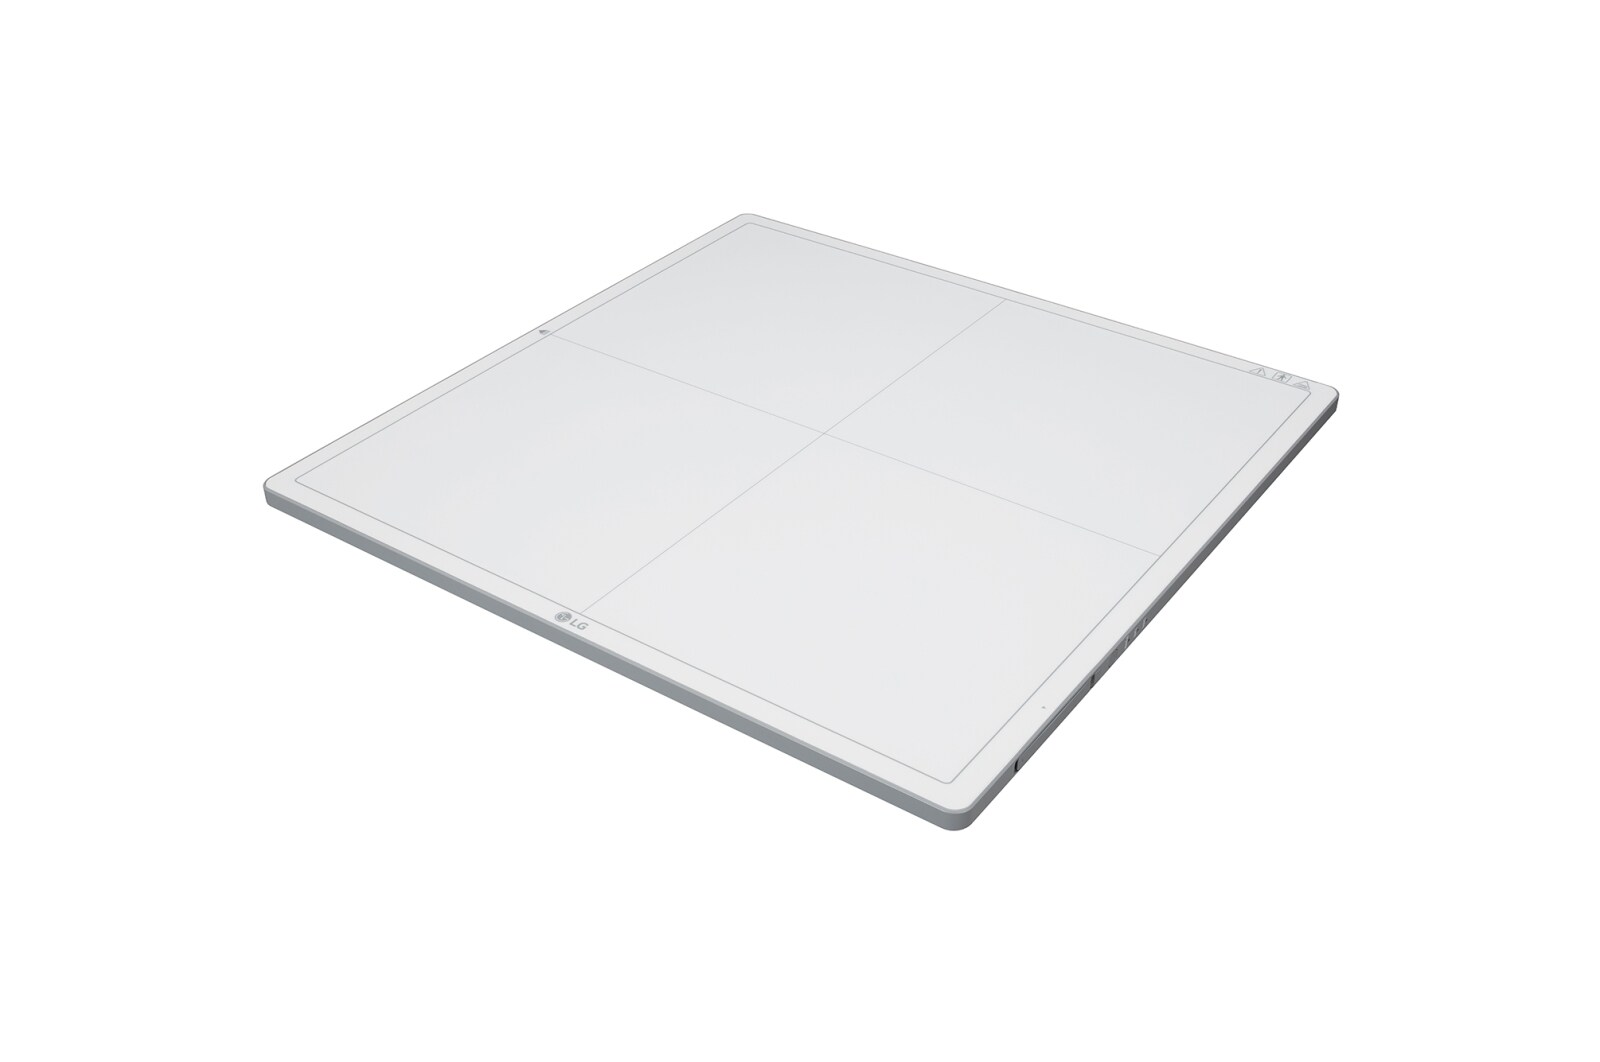

Capteur plan 17x17"

Léger mais durable

3,6 kg (7,9 lb)

Poids du produit (y compris la batterie)

300 kg (661 lb)

Charge uniforme maximale

100 kg (220 lb)

Charge locale maximale

DURABILITÉ

-

Poids maximum supporté

Full (Uniform Load) : 300 kg, 661 lbs

Local (Point Load): 100 kg, 220 lbs -

Etanchéité

IP53

-

Plaque avec Capteur de Protection

Plaque en Fibre de Carbone